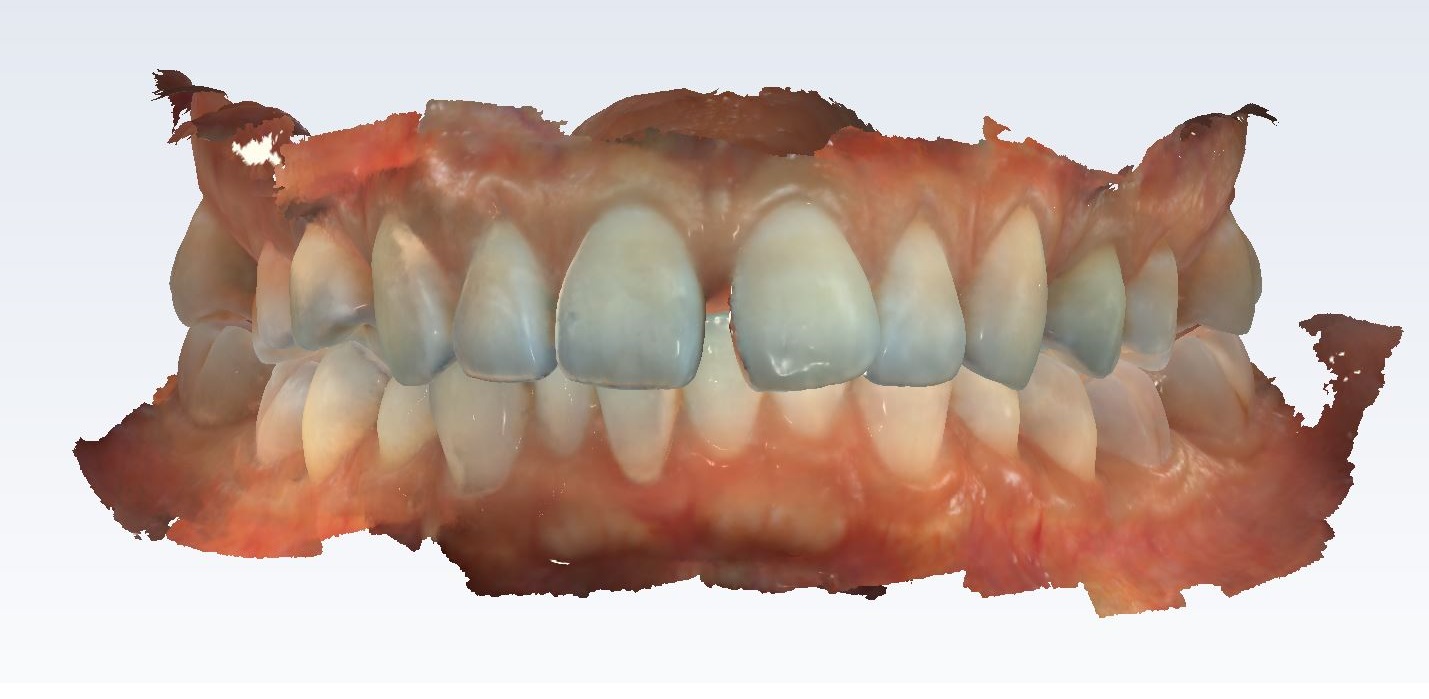

Digital Dental X-Rays

We use the advanced Nomad Pro 2, a handheld X-Ray Unit by Kavo, which is a leading brand in dental technology!

Images are crisp clean, the patient does not experience the gag feeling like the traditional X-Rays do